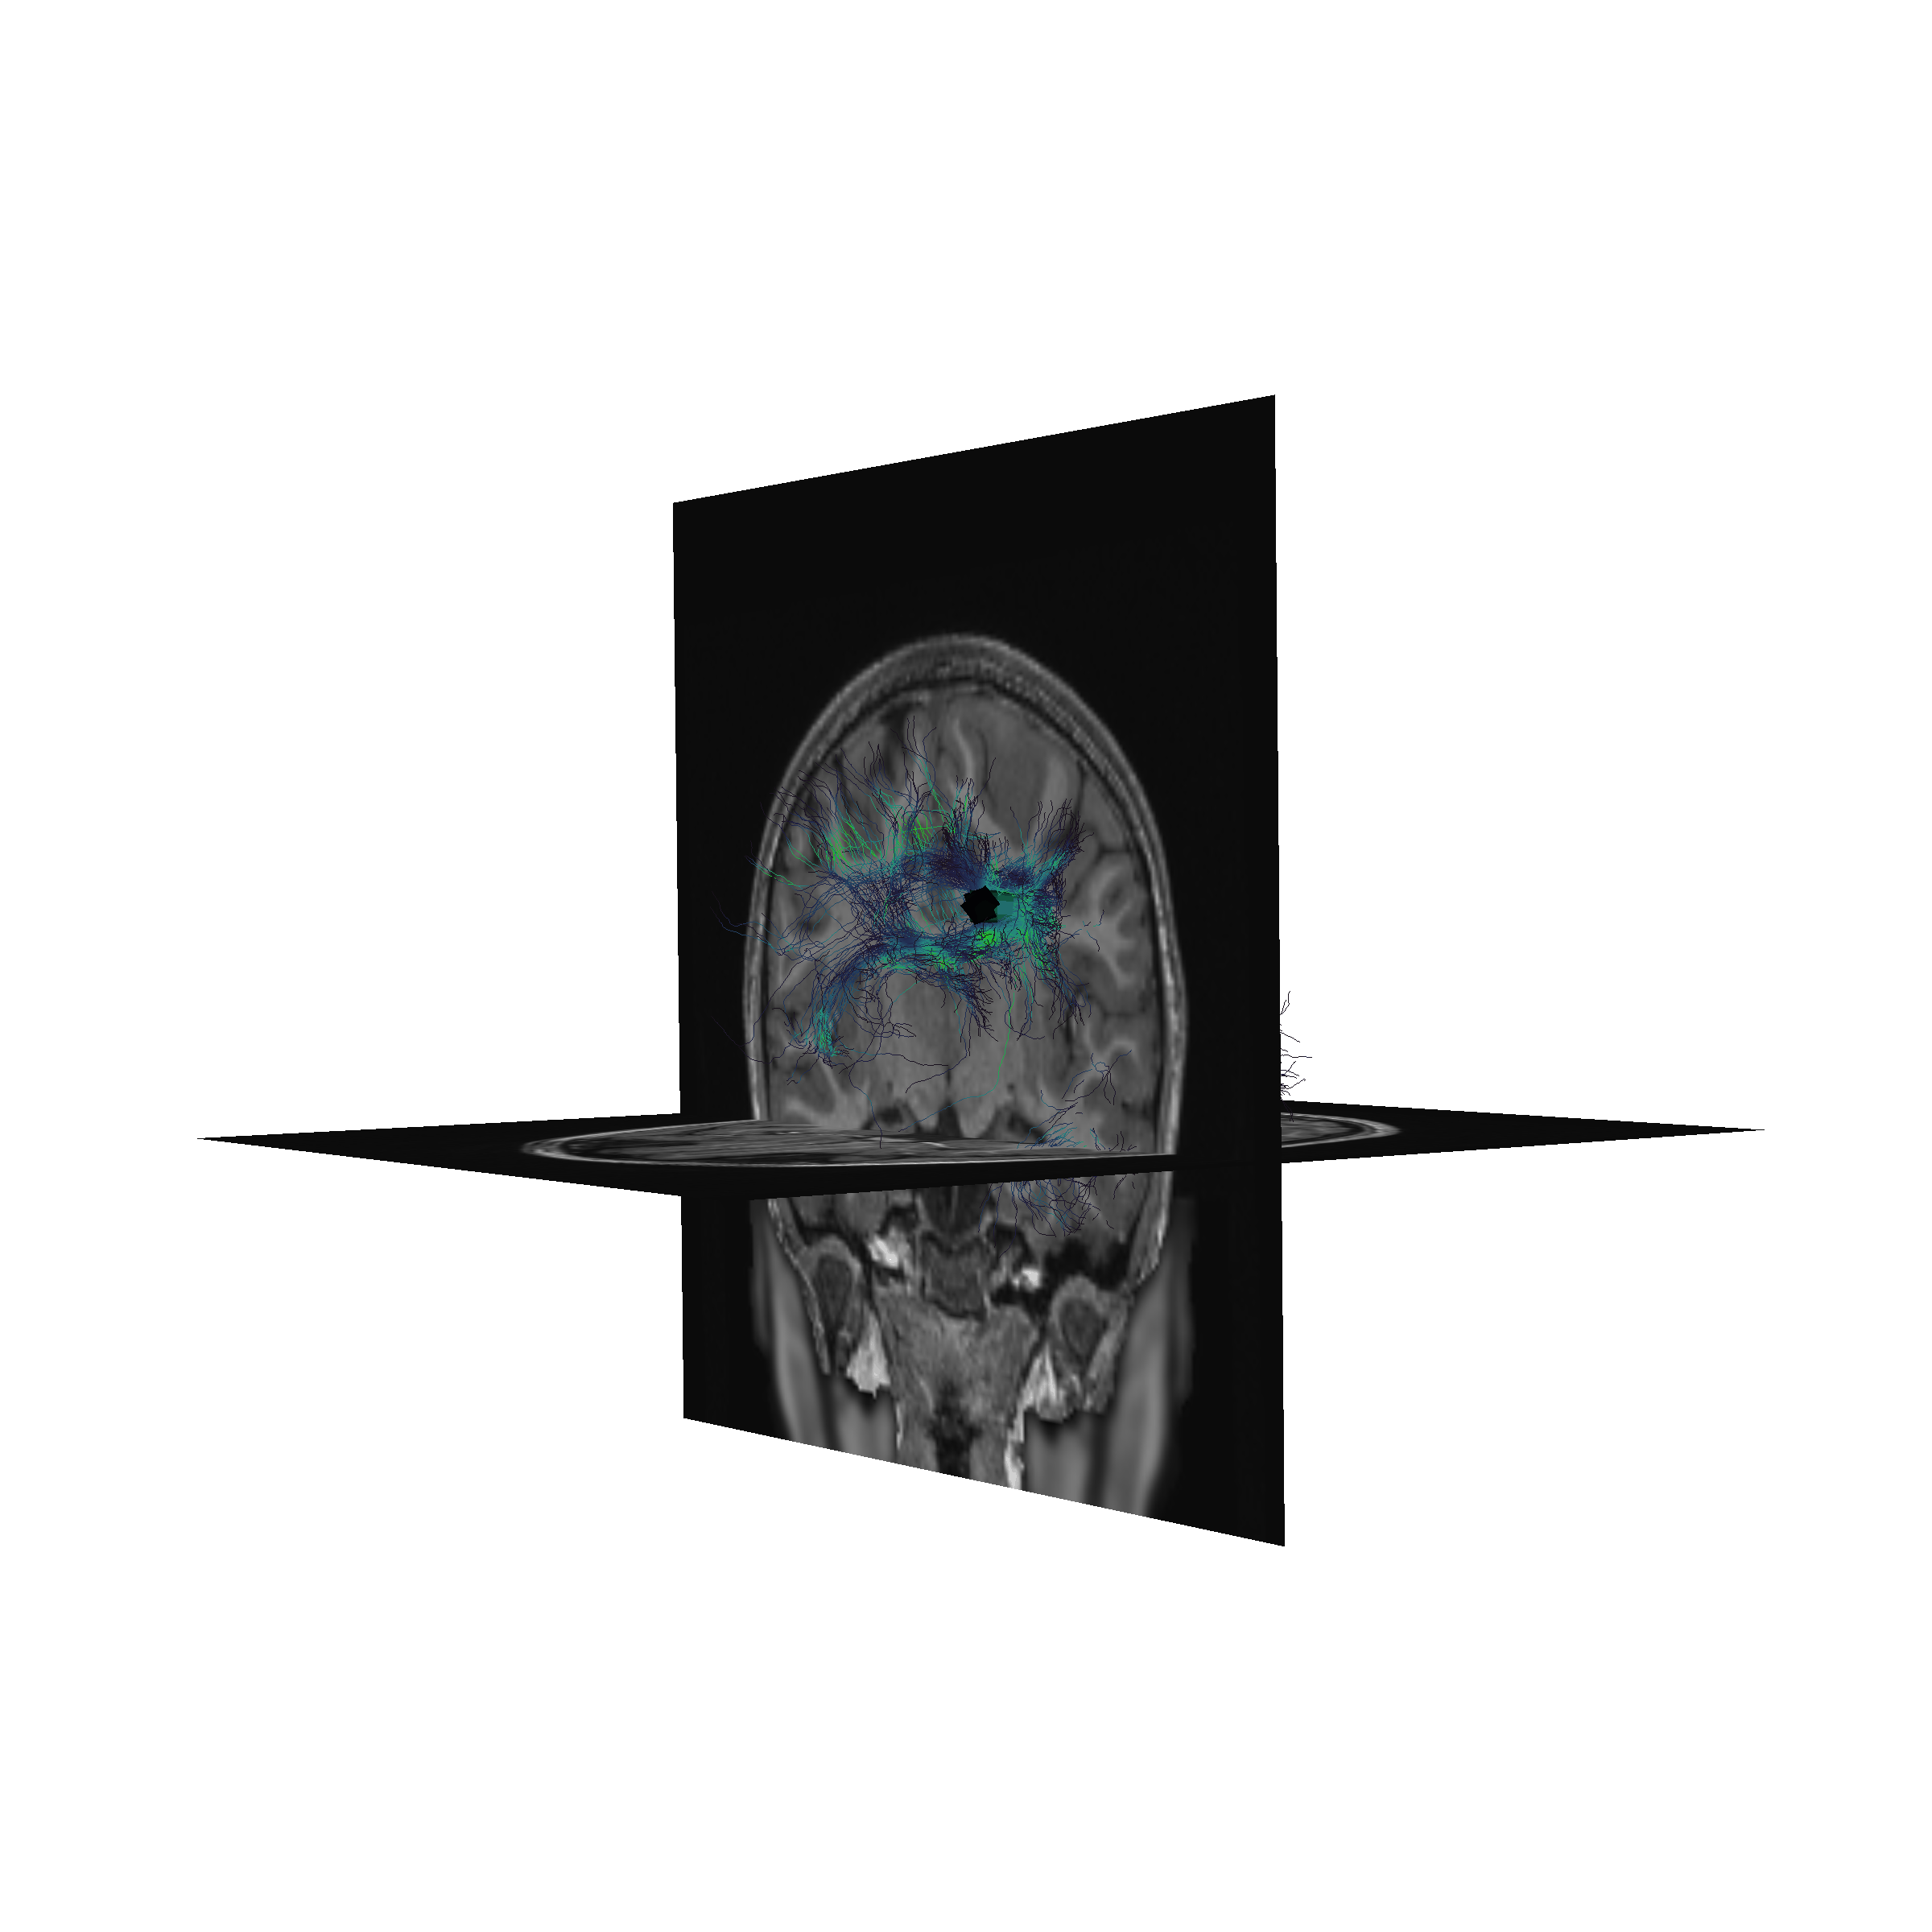

Basser (1994), Basser and Pierpaoli (1996)